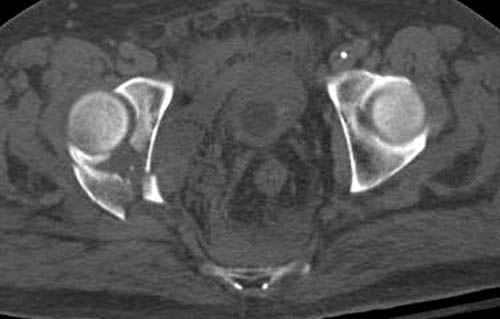

Дополнительно имеется перелом ацетабулума: задняя

колонна с полупоперечным переломом, и переломы костей лица.

На седьмой день зафиксирован перелом ацетабулума через задний доступ. Перед операцией для профилактики DVT, IVC фильтер, также получает Lovenox.

Отправитель: Evgueny Tchekashkine 30 Ноябрь 2007, 16:57

|

Джолдас,

По возможности вышлите снимки, сканы таза до реконструкции, интраоперационные.

По снимку создается впечатление о высоком поперечном переломе, задней колонны, стенки; почему не пользовались *magic screw*?

Положение больного на животе или на боку?

Кава фильтр при переломах таза - это протокол или только для пациентов с политравмой?

Фиксация таза до реконтструкции с момента поступления? Когда начали DVT профилактику: сразу при поступлении или накануне реконструкции?

По возможности вышлите снимки, сканы таза до

реконструкции, интраоперационные.

Не хотелось отклонятся от основной темы, поэтому здесь краткие ответы..

Латеральное положение облегчает проведение тракции через вертел, за 5 мм стержень за вертел (грузом через тракционное приспособление), на обычном рентгенопрозрачном операционном столе, а для положения на животе, наверное, Judet Table более приемлем, потому что там имеется латеральное тракционное устроиство.

Там множество обычных 2.7 мм шурупов, потом идет фиксация основными пластинами.